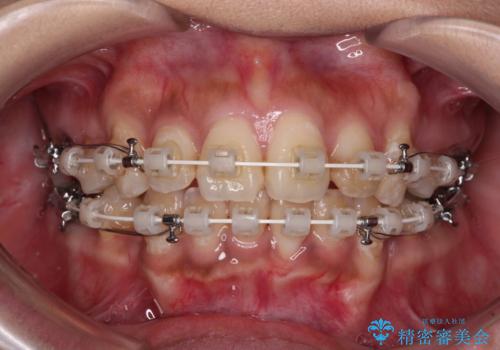

- 矯正装置

- 審美装置

- 口元の閉じにくさを気にして来院された患者様です。

上下ともに歯列が前方に突出していたため、上下左右の第一小臼歯4本を抜去し、ワイヤー装置による矯正治療を行うこととしました。

舌の突出癖による影響もあったため、舌のトレーニングを並行して実施しました。